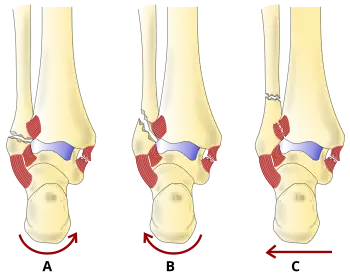

Classification

There are several classification schemes for ankle fractures:

- The Lauge-Hansen classification categorises fractures based on the mechanism of the injury as it relates to the position of the foot and the deforming force [23]

- The Danis-Weber classification categorises ankle fractures by the level of the fracture of the distal fibula (type A = below the syndesmotic ligament, type B = at its level, type C = above the ligament), with use in assessing injury to the syndesmosis and the interosseous membrane[24]